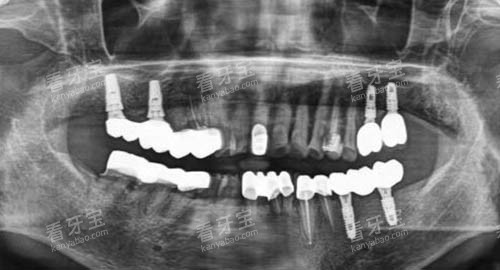

在口腔种植方面,AI 智能诊疗技术可以通过 CT 扫描获取患者口腔的三维数据,精细分析牙槽骨的密度、高度、宽度等信息,为医生制定种植方案提供更准的依据。

医生可以在计算机上模拟种植过程,提前预知种植结果,大大提高了种植的可行性和更准一些度。

同时,AI 智能导航系统可以引导医生在手术过程中更准植入种植体,减少手术创伤和并发症的发生。

在种牙方面,医院拥有多种可靠的种植系统,如瑞士 ITI 种植系统、德国 BEGO 种植系统等,能够满足不同患者的需求。

医生们根据患者的口腔情况和经济状况,为患者推荐合适的种植系统,并制定个性化的种植方案。

在手术过程中,医生们熟练掌握种植技术,确保种植手术的安心和成功。